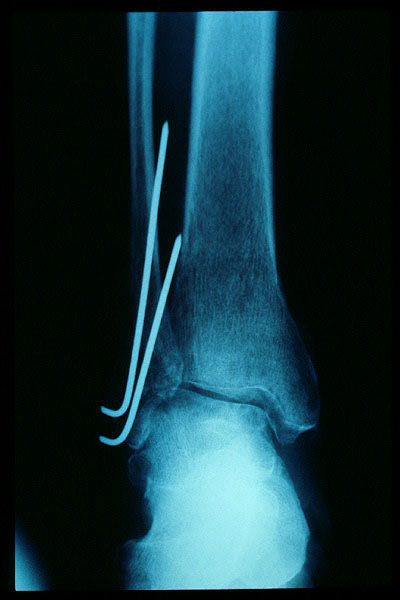

Fractura maleolo externo. Osteosíntesis.